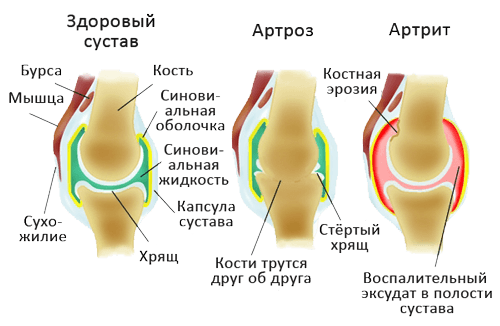

Медицинские состояния: Септический артрит коленного сустава